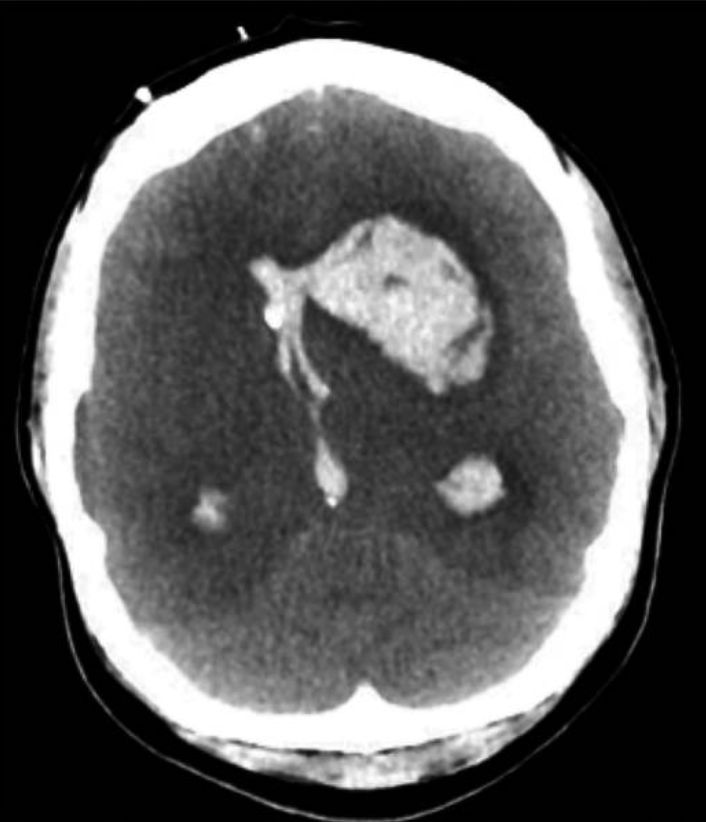

Intracerebral Hemorrhage

The most frequent occurrence of ICH in pregnancy is in the presence of hypertensive disease of pregnancy. According to autopsy studies, ICH is the primary factor in about one-third of preeclampsia-related deaths. ICH is frequently observed in conjunction with posterior reversible encephalopathy syndrome (PRES), which can occur both during and outside of pregnancy and is characterized by endothelial dysfunction, posterior-predominant vasogenic edema of the brain, and HTN.(36) Nearly all patients with eclampsia have PRES symptoms on MRI, and PRES is strongly related to eclampsia in pregnant or postpartum patients(37). Although PRES can be reversed, it can potentially lead to life-threatening side effects such as cerebral edoema and ICH; thus, it needs to be properly watched. Additionally, preexisting vascular lesions such as cerebral cavernous malformations, brain arteriovenous malformations, brain aneurysms, or unstable moyamoya collaterals may rupture and result in ICH (figure 1).(38)

Figure 1. Imaging of the patient with eclampsia and fatal ICH (38)